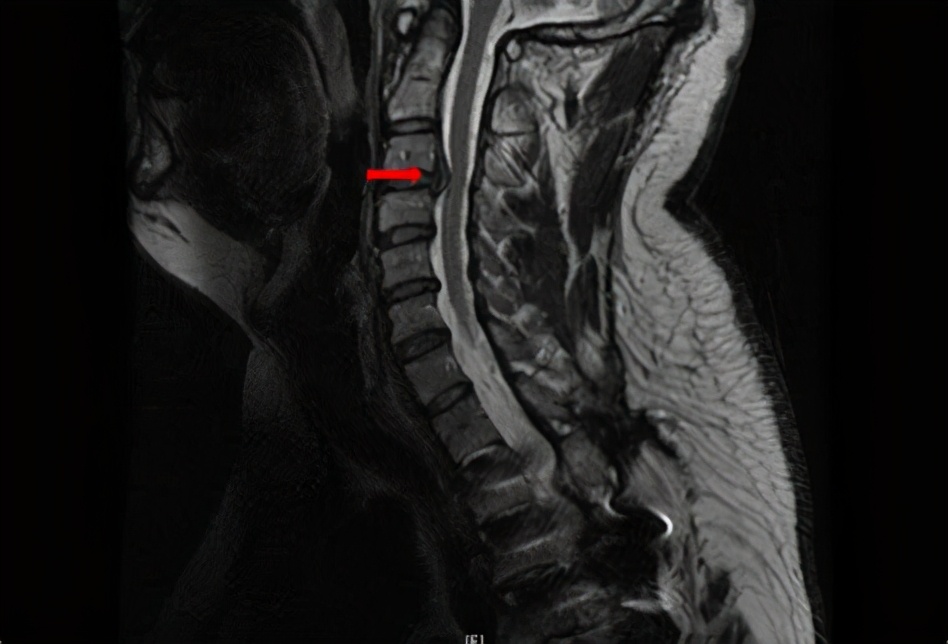

颈椎病是有很多类型的,其中有一种叫做神经根型颈椎病,就是因为压迫到了神经,导致一系列的症状和体征。这里就可能出现因为神经受压而导致的手部和胳膊麻木。

确诊的方式包括放射线检查和CT检查或者核磁共振检查,都可以看到局部神经受压的表现。